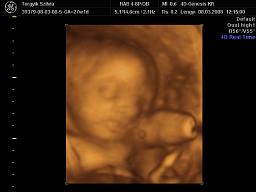

Szóval valszeg kislányod lesz! Kivi vagyok, hogy jól látta-e a dokid!